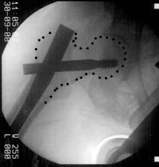

"Retrograder Nagel"